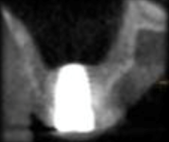

The aim of this workshop was to assess the posterior maxillary area. The posterior maxilla naturally presents low-height alveolar process, which is anatomically limited by the maxillary sinus. The roots of the molars are closely related to the floor of the maxillary sinus. In the center of the alveolar crest we find the root trifurcation area, which is the ideal site for implant placement from a prosthetic perspective, and where there is the lowest bone height in the sinus floor. This means that placing implants of standard dimensions after tooth loss

in this area is limited.

The resorption processes resulting from such loss, common to all regions of the alveolar process, may aggravate this situation. Maxillary sinus pneumatization, on account of increased osteoclastic activity along the sinus membrane and the absence of a dental “barrier” facing changes in sinus air pressure, may affect the morphology of the site. These conditions pose an anatomical challenge to the treatment of the edentulous posterior maxilla using dental implants. The techniques to repair defects in the residual alveolar ridge with autologous bone graft procedures have predictable results, which are described in the literature. A factor that explains their good results is that there are no immune reactions that may interfere with the process of tissue remodeling and development. They intrinsically have osteoblasts and growth factors responsible for the cellular changes that occur after implantation, and that end with remodeling and bone formation at the site1. Its disadvantage is the need for an additional donor surgical area which can be intraoral, in cases in which the need for reconstruction is small, or extraoral in cases of medium-sized or large reconstructions. In the 1980s, bone grafting techniques in the maxillary sinus were used to solve the problem of lack of bone, and to allow for implant placement. One of the techniques described is surgery to lift the floor of the maxillary sinus, known by its name in English: Sinus Lift2,3.

Question No. 2. Indications and factors to consider to perform a lateral approach maxillary sinus lift.

Reduced subantral bone height (5 to 8 mm) is required. Less invasive and simpler techniques are needed for specific reasons, such as: systemic problems, psychological profile or patient’s choice.

Question No. 3. Indications and factors to consider to perform a lateral approach maxillary sinus lift. Indicated in the absence of sufficient alveolar bone for implant placement with predictability in the maxillary sinus. The techniques for such a procedure would be:

Lateral window in two times: Best-documented procedure, showing long-term implant survival rates. This technique can be applied in the most diverse clinical situations, except when there are local and general contraindications for oral surgeries.

Lateral window in one time: The literature supports this procedure with implant long-term survival rates similar to the lateral window in two times technique. There is not enough scientific evidence to reach a consensus regarding a minimum bone height. To achieve good primary stability, the following minimum measures may be suggested for the subantral bone tissue: 3 mm in height and 5 mm wide9. This primary stability depends not only on quantity but also on implant quality, technique and design. Some studies show that rough surfaces have a better survival rate than machined implants10.

Crestal approach technique: Summers technique. Osteotomy is performed for the implant up to 1mm subantrally, until the sinus floor is reached with osteotomes, allowing for increases in height of 2 to 5 mm. This technique also shows high survival rates, similar to the traditional technique11. A minimum height of 5 mm of residual bone is recommended9. A problem with this technique is that the perforation of the membrane may go unnoticed, so placing bone substitutes is recommended11.